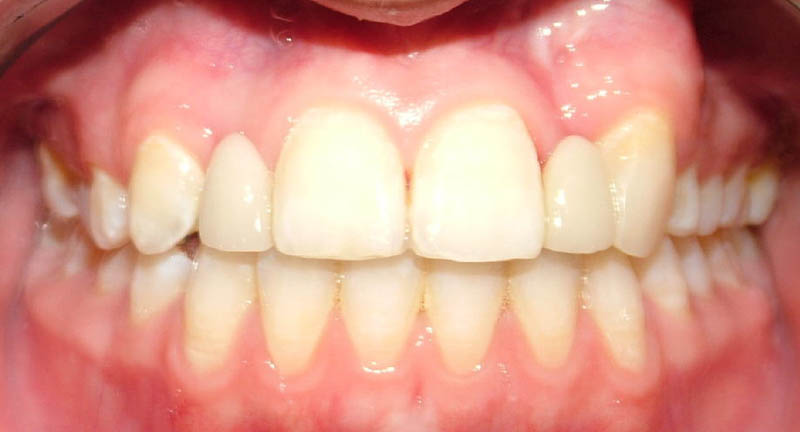

În aprilie 2009, după 37 luni de tratament, au fost îndepărtate aparatele fixe (fig. 6). Pentru contenţie, s-a aplicat un retainer fix colat pe faţa linguală a celor şase dinţi frontali inferiori şi o placă palatinală Hawley care încorporează dinţi acrilici în dreptul incisivilor laterali pentru a menţine un aspect estetic până când medicul protetician va putea realiza punţile dentare. În plus, s-a utilizat un arc vestibular care să consolideze contenţia şi care să permită aplicarea unor forţe uşoare, cu direcţie linguală, dacă este necesar.25 Croşetele ”în deget” sunt situate distal de incisivii centrali maxilari şi mezial de caninii superiori, pentru a permite o deplasare discretă mezio-distală a dinţilor, dacă este necesar (fig. 7).Înainte de îndepărtarea aparatului, a fost consultat medicul protetician. S-a pus problema dacă pacienta ar avea dificultatea de a purta pe termen lung un aparat mobil de contenţie, din cauza dificultăţilor de respiraţie şi a tusei, asociate cu fibroza chistică. În plus, din cauza anodonţiei de incisivi laterali superiori, osul alveolar este dezvoltat insuficient şi prezintă, astfel, dimensiuni prea reduse pentru inserarea implantelor dentare; procedura de augmentare a ţesuturilor moi şi dure ale crestei alveolare ar fi inevitabilă. Vârsta pacientei şi creşterea şi dezvoltarea corespunzătoare au fost, de asemenea, luate în considerare.19 Ortopantomograma finală relevă anodonţia molarilor de minte inferiori şi a celui superior drept pe lângă anodonţia incisivilor laterali maxilari şi a premolarului secund drept inferior. De asemenea, se remarcă aplatizarea rădăcinilor incisivilor centrali maxilari, care era prezentă şi pe radiografia efectuată înainte de tratament (fig.8).

Punţile metalo-ceramice cu agregare adezivă, au fost alese pentru restaurările protetice finale. Acest tip de restaurare are următoarele caracteristici: utilizarea metalelor preţioase, utilizarea tehnologiei de ardere a ceramicii pe suport metalic şi adeziunea ceramicii gravate la suprafeţele dentare.26 Puntea metalo-ceramică cu agregare adezivă reprezintă o modificare a punţii Maryland24 şi necesită o preparare minimă, conservativă a dintelui, care nu depăseşte grosimea smalţului. Spre deosebire de puntea Maryland, nu au fost semnalate umbrele întunecate incizale şi nici descimentările frecvente.23 Rezistenţa punţii este dată de un schelet turnat din metal preţios. Întrucât ar fi de dorit să existe un spaţiu interincizal pentru scheletul metalic, medicul ortodont a urmărit obţinerea unui spaţiu de 1mm între feţele palatinale ale incisivilor centrali superiori şi marginile incizale vestibulare ale incisivilor centrali inferiori (fig. 9). Suprafeţele aripioarelor punţii, corespunzătoare dinţilor stâlpi, sunt formate din ceramică arsă pe scheletul metalic subiacent, care aderă adeziv la smalţul palatinal al dinţilor stâlpi. Procesul de cimentare a inclus: gravarea acidă şi aplicarea unui primer de smalţ/dentină pe suprafeţele dentare, gravarea cu acid fluorhidric, curăţarea şi aplicarea silanului la nivelul feţelor palatinale ale ambelor punţi şi cimentarea cu un sistem autopolimerizabil total (fig. 11). Pacienta era preocupată de “vizibilitatea metalului strălucitor” din spatele dinţilor frontali în surâs. Din această cauză, toate suprafeţele metalice au fost sablate înainte de cimentare.

Medicul protetician a dorit ca, la sfârşitul tratamentului ortodontic, linia interincisivă superioară să coincidă cu mediana feţei, care era deviată spre dreapta cu 1mm faţă de linia interincisivă inferioară.27 Planul de tratament include, de asemenea, remodelarea cu compozite la nivelul caninului stâng prin metoda directă, ameloplastie realizată cu scopul de a crea o asemănare acceptabilă între cei doi dinţi vecini. Pacienta a urmat, sub supravegherea medicului dentist, procedura de albire a dinţilor naturali la domiciliu, utilizând gutiere individualizate28 pe durata nopţii, timp de 3 săptămâni. S-a folosit un gel de peroxid de carmabidă în concentraţie de 16%, aplicat în gutiere individualizate vacuum-formate. Procedura de albire a fost iniţiată după aplicarea finală a punţilor, astfel că pacienta va avea un etalon al culorii în vederea efectuării unor albiri viitoare. Pentru aceasta a fost necesar să se estimeze o nuanţă finală a corpurilor de punte înainte de efectuarea albirii dentare (fig. 12).

Când pacienta s-a prezentat la control câteva săptămâni mai târziu, s-a observat apariţia unei diasteme de 0,5mm (fig. 13, 14). Medicul protetician a reechilibrat feţele palatinale ale restaurărilor şi ale dinţilor stâlpi, iar medicul ortodont a aplicat o placă Hawley de contenţie, ce prezintă un arc vestibular în contact cu feţele vestibulare ale tuturor dinţilor. S-a îndepărtat din acrilat în dreptul feţelor linguale ale incisivilor centrali, iar arcul a fost activat la nivelul incisivilor centrali astfel încât să exercite asupra acestora forţe uşoare direcţionate în sens lingual (fig. 15). Diastema a putut fi închisă cu ajutorul plăcii Hawley, iar ulterior medicul protetician a aplicat, printr-o metodă conservatoare, un retainer fix, colat intracoronal între porţiunile meziale vecine ale feţelor palatinale ale incisivilor centrali superiori. A fost fixat un ştift de aur cu ajutorul unei răşini compozite, menţinând placa Hawley în cavitatea orală, pentru a nu-i compromite stabilitatea. Ulterior, toate contactele de la nivelul incisivilor centrali, înregistrate în poziţii centrice şi în mişcări de lateralitate şi de propulsie, au diminuate până au devenit slabe. Pacienta şi-a exprimat dorinţa ca ambrazura incizală să fie mai redusă, aşa încât aceasta a fost închisă parţial cu ajutorul suprafeţei vestibulare a retainerului fix (fig. 16, 17). Pacienta şi părinţii au fost mulţumiti de rezultatul final obţinut.